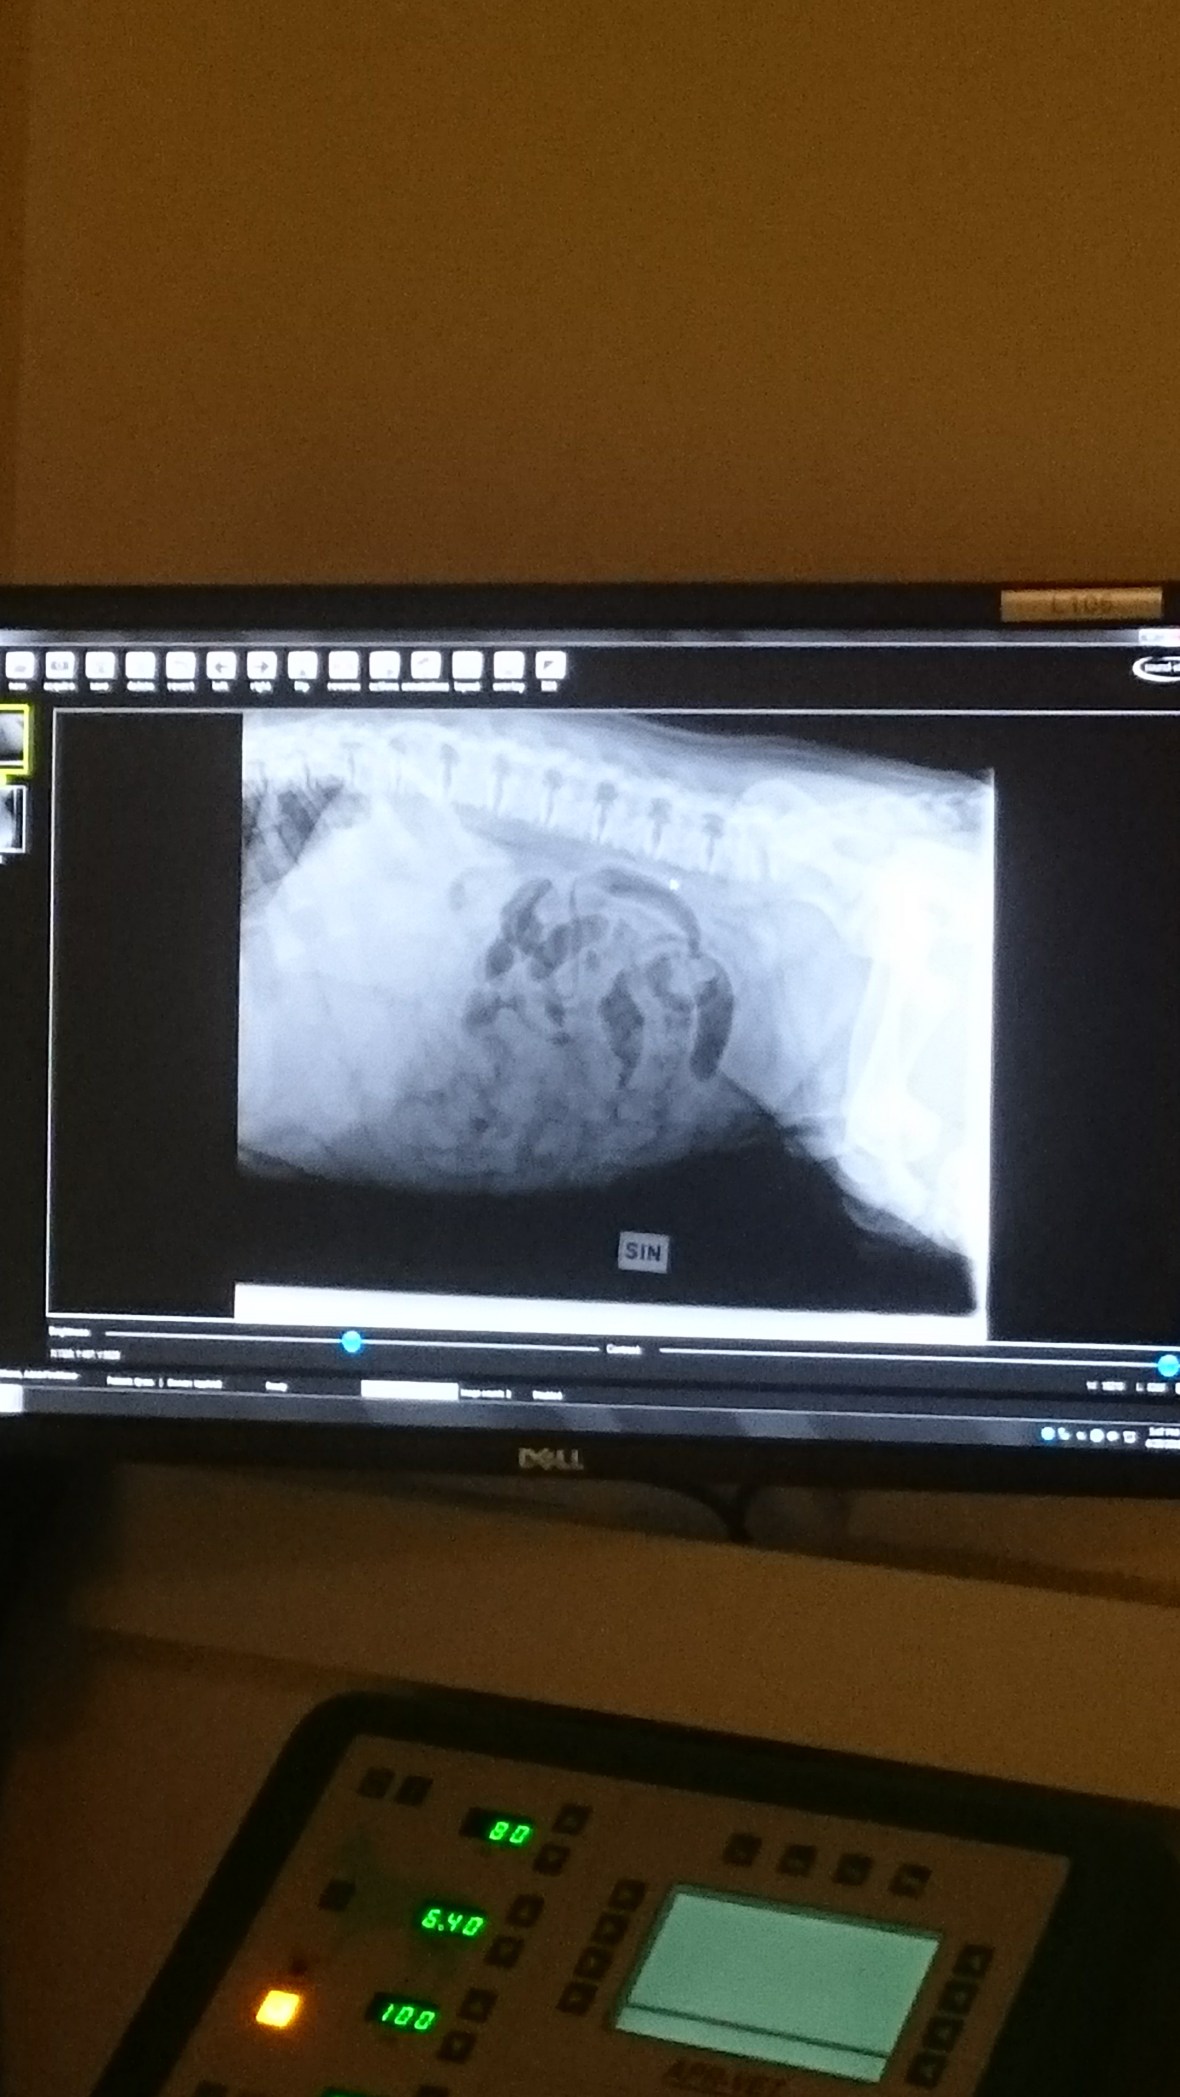

Det var inte akut med uttorkning men han hade feber 39,2 buken kändes relativt mjukt men det beslutades om röntgen för att se om nåt fanns på insidan som inte skulle vara där.

Mycket gaser i magen och något som tydde på benfragment eller ev grus.